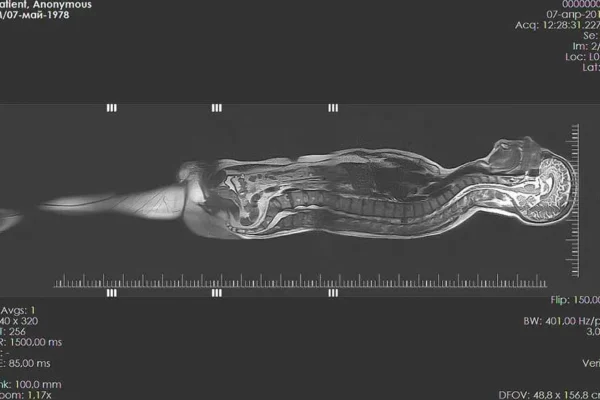

- Emar

- Tüm Vücut MR